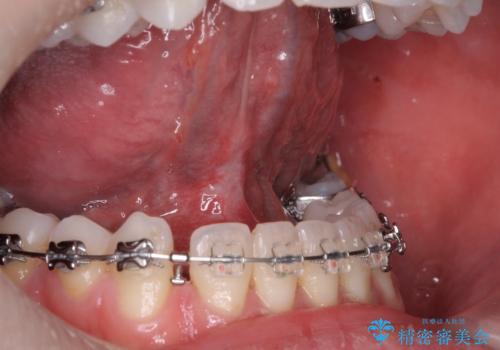

[ 舌小帯形成術 ]舌が短い 小手術での改善

担当医 大元洋佑

![[ 舌小帯形成術 ]舌が短い 小手術での改善の症例 治療前](https://seimitsushinbi.jp/wp/wp-content/uploads/2022/06/8d267ea0a8ffaaf134998cbb95ac3e27-500x350.jpg?v=1654757892)

![[ 舌小帯形成術 ]舌が短い 小手術での改善の症例 治療後](https://seimitsushinbi.jp/wp/wp-content/uploads/2022/06/IMG_9990-2-500x350.jpg?v=1654757908)